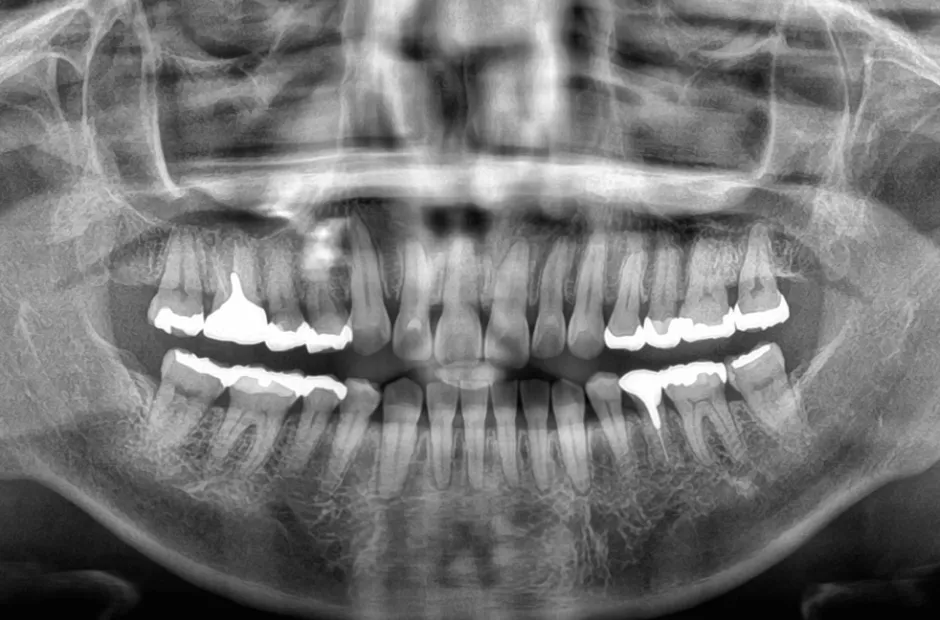

叢生

| 診断名・主訴 | 叢生 |

|---|---|

| 年齢・性別 | 43歳・女性 |

| 治療期間・回数 | 2年7か月 27回 |

| 治療に用いた主な装置 | 舌側矯正 |

| 抜歯部位 | 両顎4,4 |

| 治療費 | 100万円(税抜) |

| リスク・副作用 | 装置による違和感・疼痛・歯肉退縮・歯根吸収・虫歯のリスクなど |

治療後